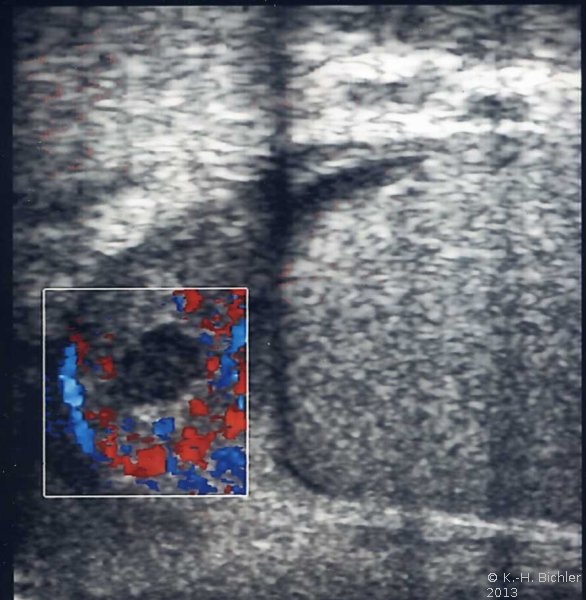

Sonographie: Vergrößerter und destruierter Nebenhoden (Abbildung 2).